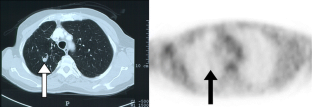

Fig. 1